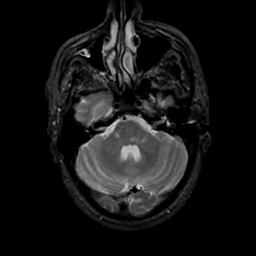

MR Study #17, July 7, 1991 -- Slice #12